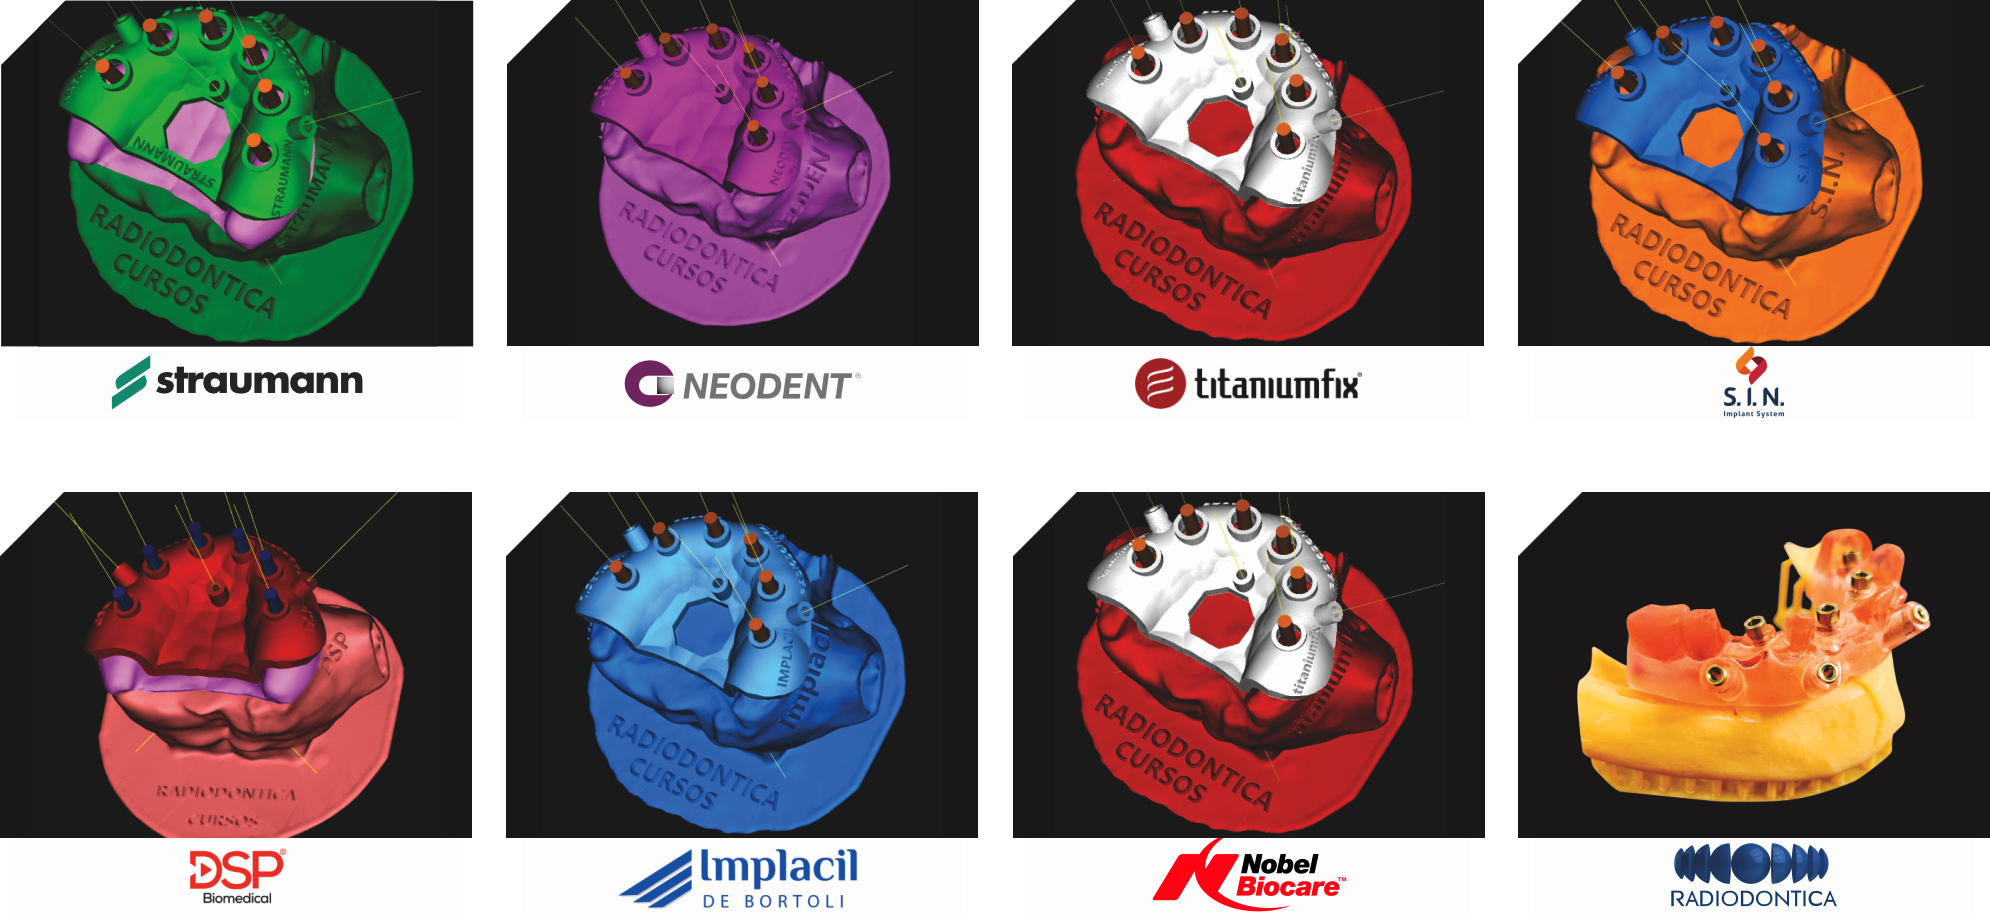

É o procedimento da realização de implante(s) de maneira guiada, com total segurança, uma cirurgia com possibilidade de não haver cortes, reduzido sangramento e pós-operatório rápido e na grande maioria das vezes totalmente indolor. Para obter o guia é necessário fazer tomografia e escaneamento da arcada dentária. Com esses exames e um software de planejamento será feito o planejamento em 3D dos implantes e gerado uma guia de implantes, a qual será posicionado em boca para direcionar a correta perfuração e instalação dos implantes. A precisão do posicionamento dos implantes com o uso do guia, permite, além dos benefícios cirúrgicos, que o(s) dente(s) da prótese já possam ser confeccionados previamente, e já estarem prontos para serem instalados no dia da cirurgia.